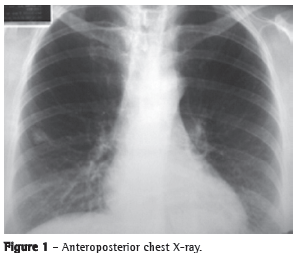

Computed tomography of the ch parts and lobulated borders, measuring 2.0 × 1.5 cm and located in the lateral segment of the middle lobe. There were no enlarged mediastinal lymph nodes (Figure 2).